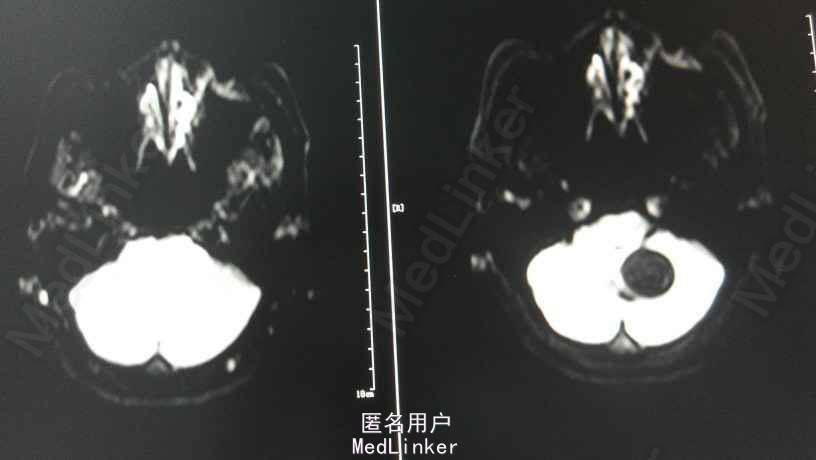

头颅MRA:小脑蚓部占位,血管母细胞溜可能性大;左椎动脉颅内段局部轻度狭窄;左侧大脑前动脉A1段稍细。

感谢分享这么罕见的病例。这位患者的临床表现包括1、(影像学)小脑血管母细胞瘤;2、腹腔脏器病变(肾脏占位和胰腺多发囊肿),VHL综合征的考虑应该没有什么问题,不...查看全部